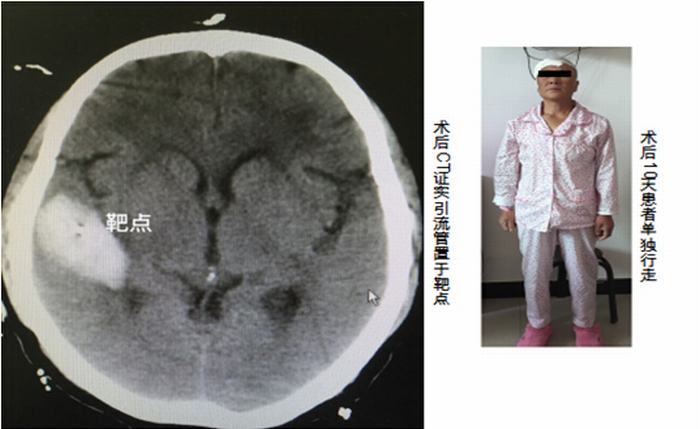

手術一小時,頭痛、肢體活動受限等癥狀全部說“再見”。這樣的奇遇,最近就發(fā)生在咸陽市閆女士的身上,得益于我院神經(jīng)外科成功開展首例腦立體定向手術,閆女士的生活發(fā)生著可喜的重大變化。

術前安裝定位頭架后進行CT掃描

2016年4月21日凌晨2點,閆女士突然出現(xiàn)頭痛、左側肢體無力等癥狀,當晚即被家人緊急送醫(yī),經(jīng)查,她大腦的右側顳葉出現(xiàn)腦出血。經(jīng)過細致的準備,我院神經(jīng)外科醫(yī)護人員為閆女士實施了腦立體定向手術,術前安裝頭架,頭顱CT掃描,設定靶點并計算坐標,術中安裝弓形架等,將引流管精確植入靶點---血腫正中心,順利抽出血腫,術后CT驗證立體定向手術精確。現(xiàn)經(jīng)治療10多天后患者已獨立下床活動,恢復理想。